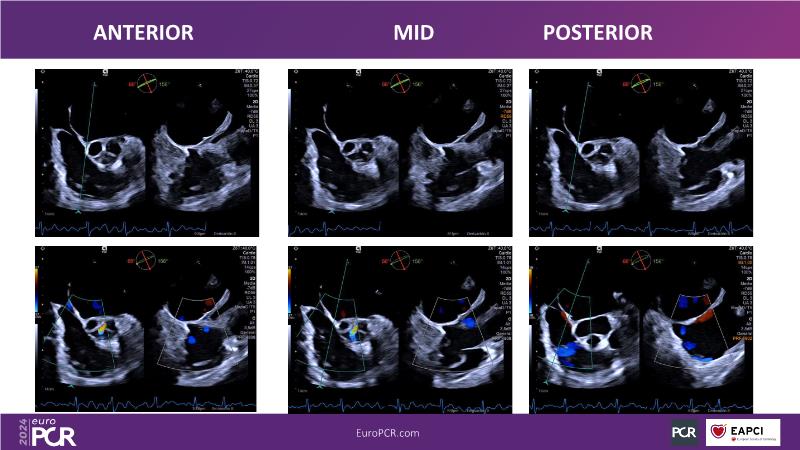

Transformative imaging in the clinical pathway of transcatheter tricuspid valve interventions

Explore this EuroPCR 2024 session for a comprehensive understanding of the imaging pathway in transcatheter tricuspid valve interventions, including diagnosis, therapy, and post-procedural follow-up, discover innovative, transformative imaging techniques such as 4D intracardiac echocardiography and dual-source photon-counting CT, and learn how these innovations can be applied in clinical practice.

- To gain a complete overview of the imaging pathway for transcatheter tricuspid valve interventions (from diagnosis to therapy to post-procedural follow-up)

- To learn innovative, transformative imaging techniques in transcatheter tricuspid interventions (e.g. 4D intracardiac echocardiography, dual source photon-counting CT)

- To illustrate the potential of these technologies in everyday clinical practice